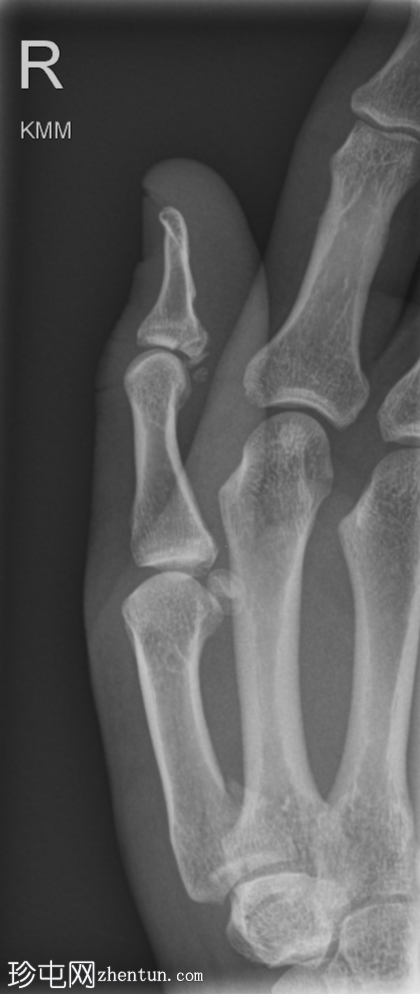

斜位

右拇指远节指骨掌侧关节内轻度移位骨折,可能为撕脱性骨折。关节内可见轻微皮质台阶。

第一掌骨基底部可见轻微移位骨折,根据骨折轨迹推测可能为关节内骨折,但关节内皮质台阶不明显。若临床治疗方案改变,可能需要进一步

影像

学检查。第一腕掌关节解剖对位良好。